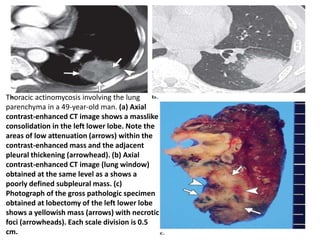

Thoracic actinomycosis involving the lung

parenchyma in a 49-year-old man. (a) Axial

contrast-enhanced CT image shows a masslike

consolidation in the left lower lobe. Note the

areas of low attenuation (arrows) within the

contrast-enhanced mass and the adjacent

pleural thickening (arrowhead). (b) Axial

contrast-enhanced CT image (lung window)

obtained at the same level as a shows a

poorly defined subpleural mass. (c)

Photograph of the gross pathologic specimen

obtained at lobectomy of the left lower lobe

shows a yellowish mass (arrows) with necrotic

foci (arrowheads). Each scale division is 0.5

cm.